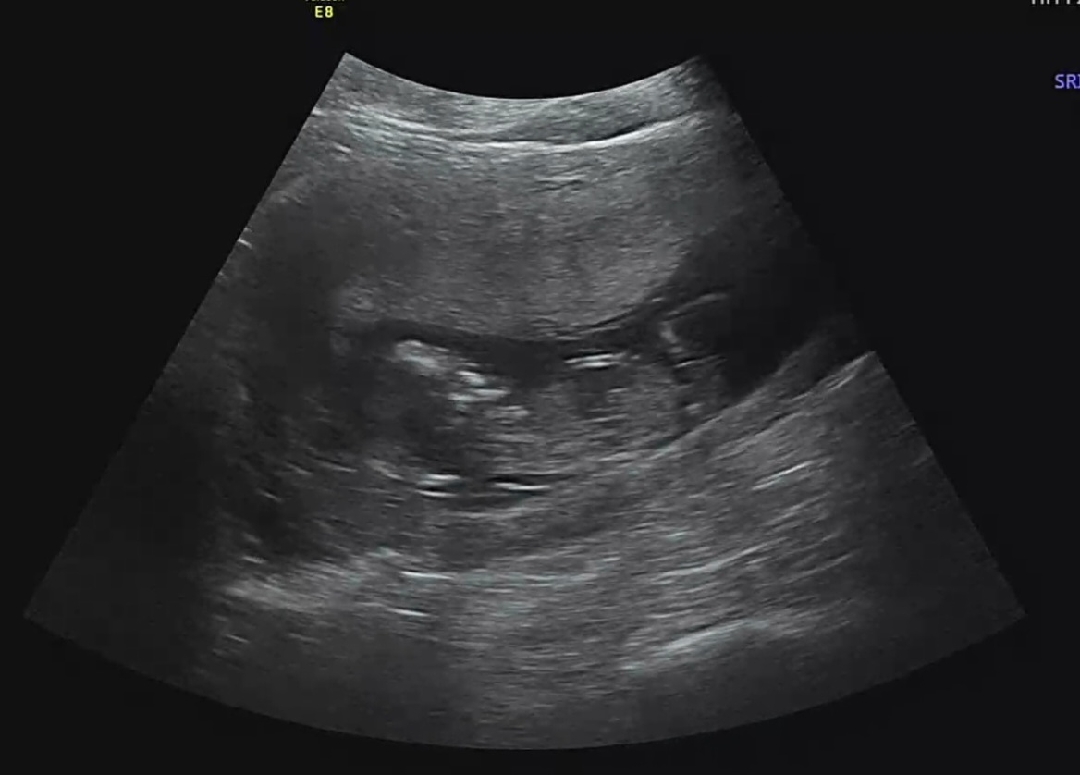

각도법 잘보시는분!! 봐주세요ㅠㅠ

각도법 좀 봐주세요!!